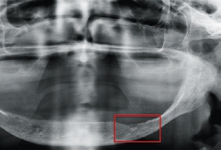

Bei der 79-jährigen Patientin, Nichtraucherin und nicht alkoholabhängig, erfolgte die initiale Diagnosestellung im März 2015. Bei der klinischen Untersuchung zeigte sich eine exophytische Läsion im III. Quadranten und es lag ein starker Verdacht auf ein Plattenepithelkarzinom mit Infiltration des UK vor (Abb. 2 u. 3). Der radiologische Befund ließ eine Tumorinfiltration des perios-talen Gewebes und Arrosion des kortikalen Knochens vermuten, ohne Infiltration der Spongiosa, pT3, pN1, G2 (Abb. 4–8). Die Diagnose lautete: mäßig differenziertes, keratinisiertes, invasives Plattenepithelkarzinom.